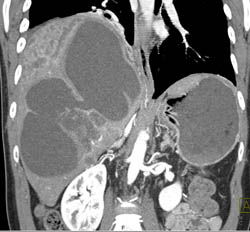

Biliary Cystadenocarcinoma